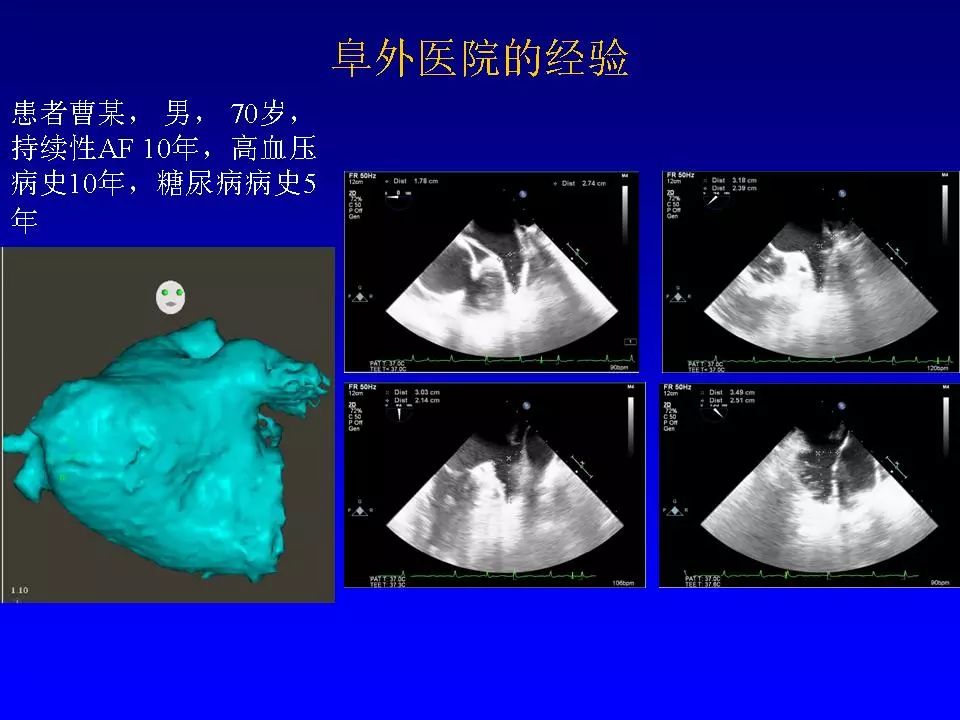

在2018老年冠心病学习班上,阜外医院心律失常中心的方丕华教授从房颤的分类、治疗策略和介入治疗方法入手,与大家分享了房颤介入治疗技术的个体化应用策略